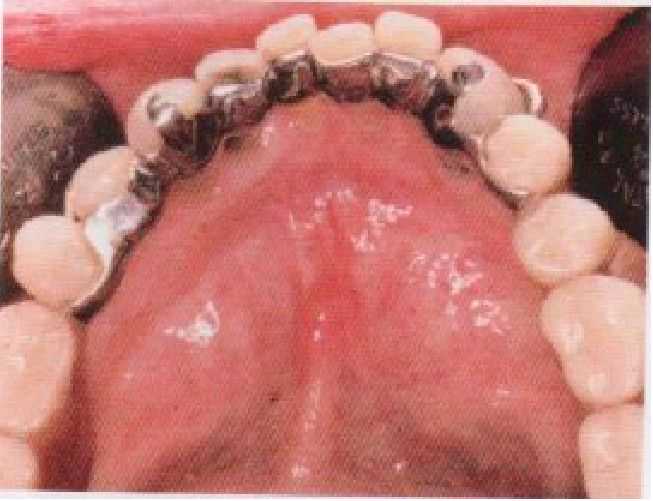

Это позволяет создать достаточную опору и стабилизацию, а также обеспечить эффективную непрямую ретенцию. В частности, язычный литой базис показан, когда прогноз относительно некоторых сохранившихся зубов сомнителен. При этом последующее добавление зубов к язычной пластинке уже имеющихся съемных протезов становится относительно несложным. При незначительных промежутках между веерообразно разошедшимися передними зубами на язычном литом базисе могут быть вырезаны выемки соответственно их проекциям. Это делает металл базиса невидимым для окружающих (см. рис. 5-76).